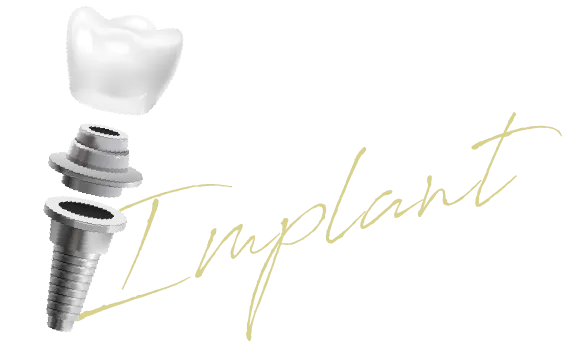

04

インプラント

埋入本数

300本以上

専修医による

インプラント

埋込本数

300本以上

日本口腔インプラント学会専修医による治療

失った歯を補うインプラント治療において、最も重要なのは「安全性」と「確実性」です。当院では、インプラント治療を専門的に学び、日本口腔インプラント学会から「専修医」の認定を受けたドクターが担当します。

院内に完備した歯科用CTで骨の状態を三次元的に解析し、専用ソフトでシミュレーションを行った上で、インプラント専門ドクターが執刀。この徹底したプロセスにより、難症例への対応はもちろん、将来を見据えた長持ちするインプラントを実現します。

「インプラント治療を受けたいけれど、どの歯医者を選べばいいのか分からない」——そんなお悩みをお持ちではありませんか。

インプラントは決して安い治療ではありません。だからこそ、信頼できる歯科医師のもとで治療を受けたいと思うのは当然のことです。当院には日本口腔インプラント学会の専修医が在籍しており、親知らずの抜歯を得意とする歯科医師もおりますので、外科処置を伴う治療も安心してお任せいただけます。

また、「骨が足りない」「難しいケースだ」と他院で断られた方も、どうぞ一度ご相談ください。セカンドオピニオンとしてのご相談も歓迎しております。別の視点や治療法によって対応できる場合もありますので、まずはお気軽にお問い合わせください。

諦める前に、当院の「インプラント専修医」にご相談ください。当院には日本口腔インプラント学会の「専修医」が在籍しており、骨を増やす処置(骨造成)などの難症例にも対応できる体制を整えています。

院内の歯科用CTで骨の状態を詳細に解析し、セカンドオピニオンとして別の治療プランをご提案できる可能性があります。「近所の医院」でありながら、専門的な技術を提供いたします。